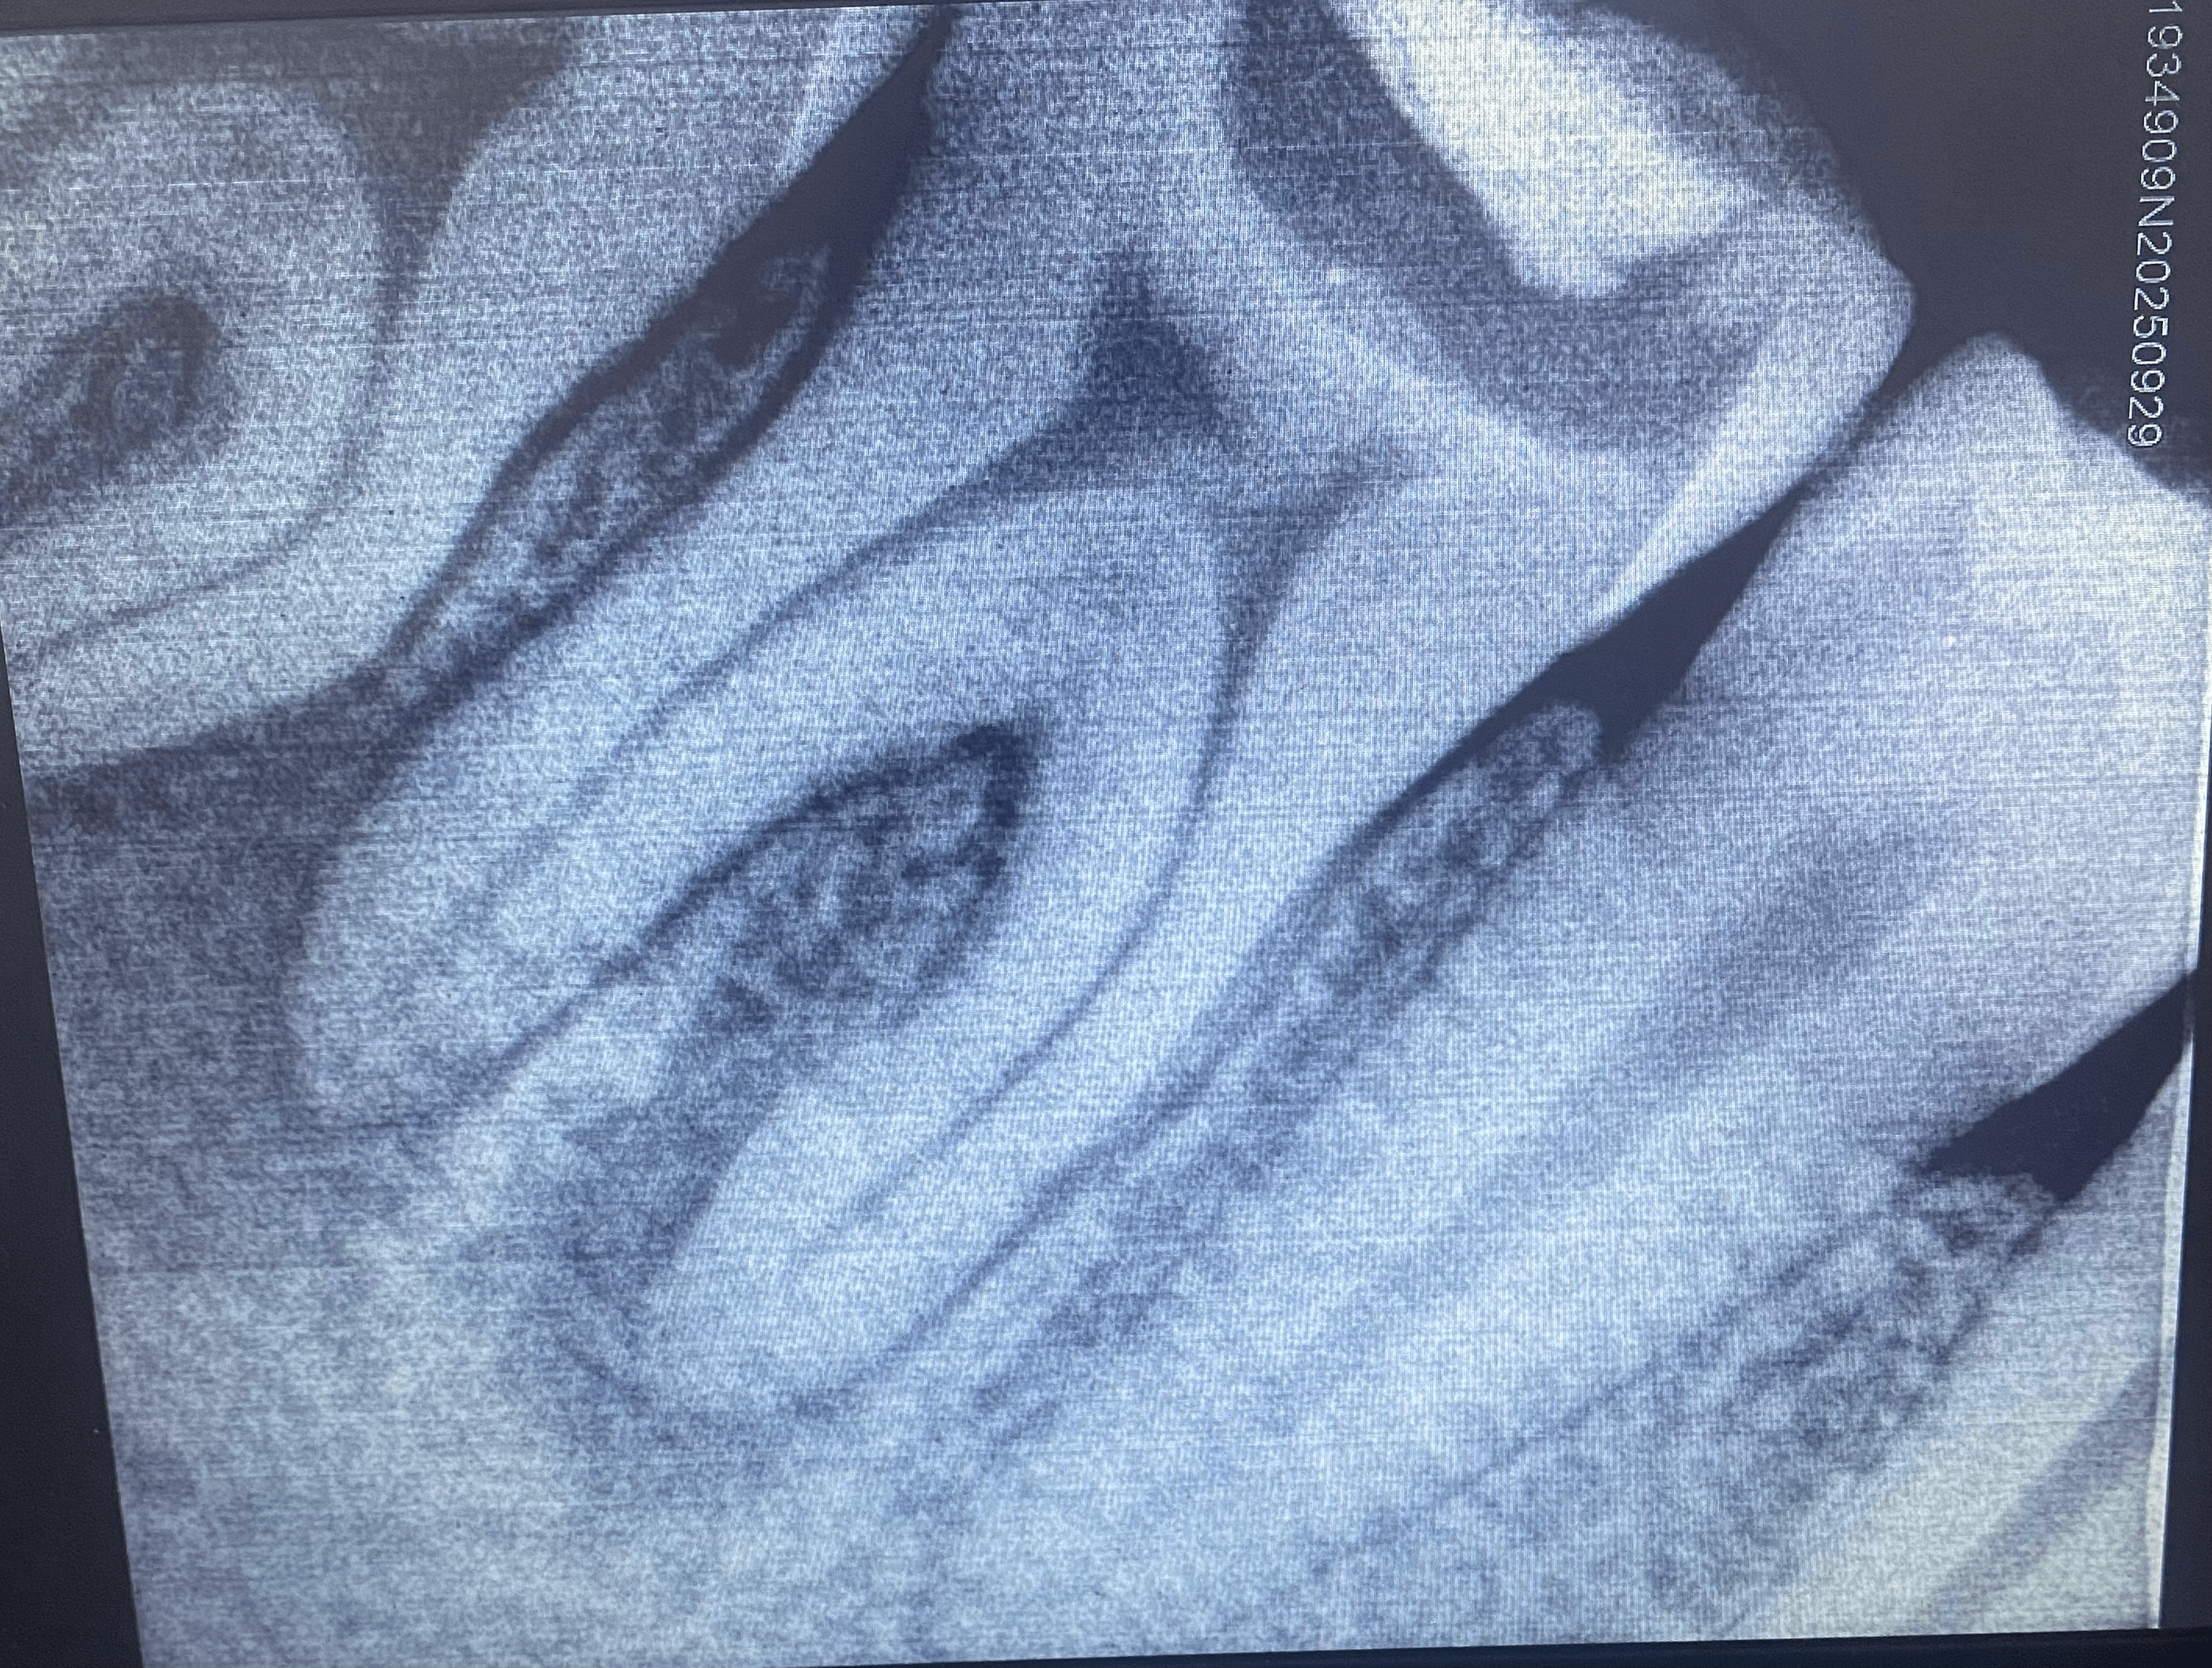

I took one look at that fucked up mouth and knew that I needed to get a dental check up and now I've learned that I need to get that teeth pulled because cavities have been brewing in it for years and my body never really alerted me because it has gotten used to the pain.

I think I'll just take out a loan so I can get this over with today, I'll share a picture of the extracted tooth with a spoiler warning on the discord.